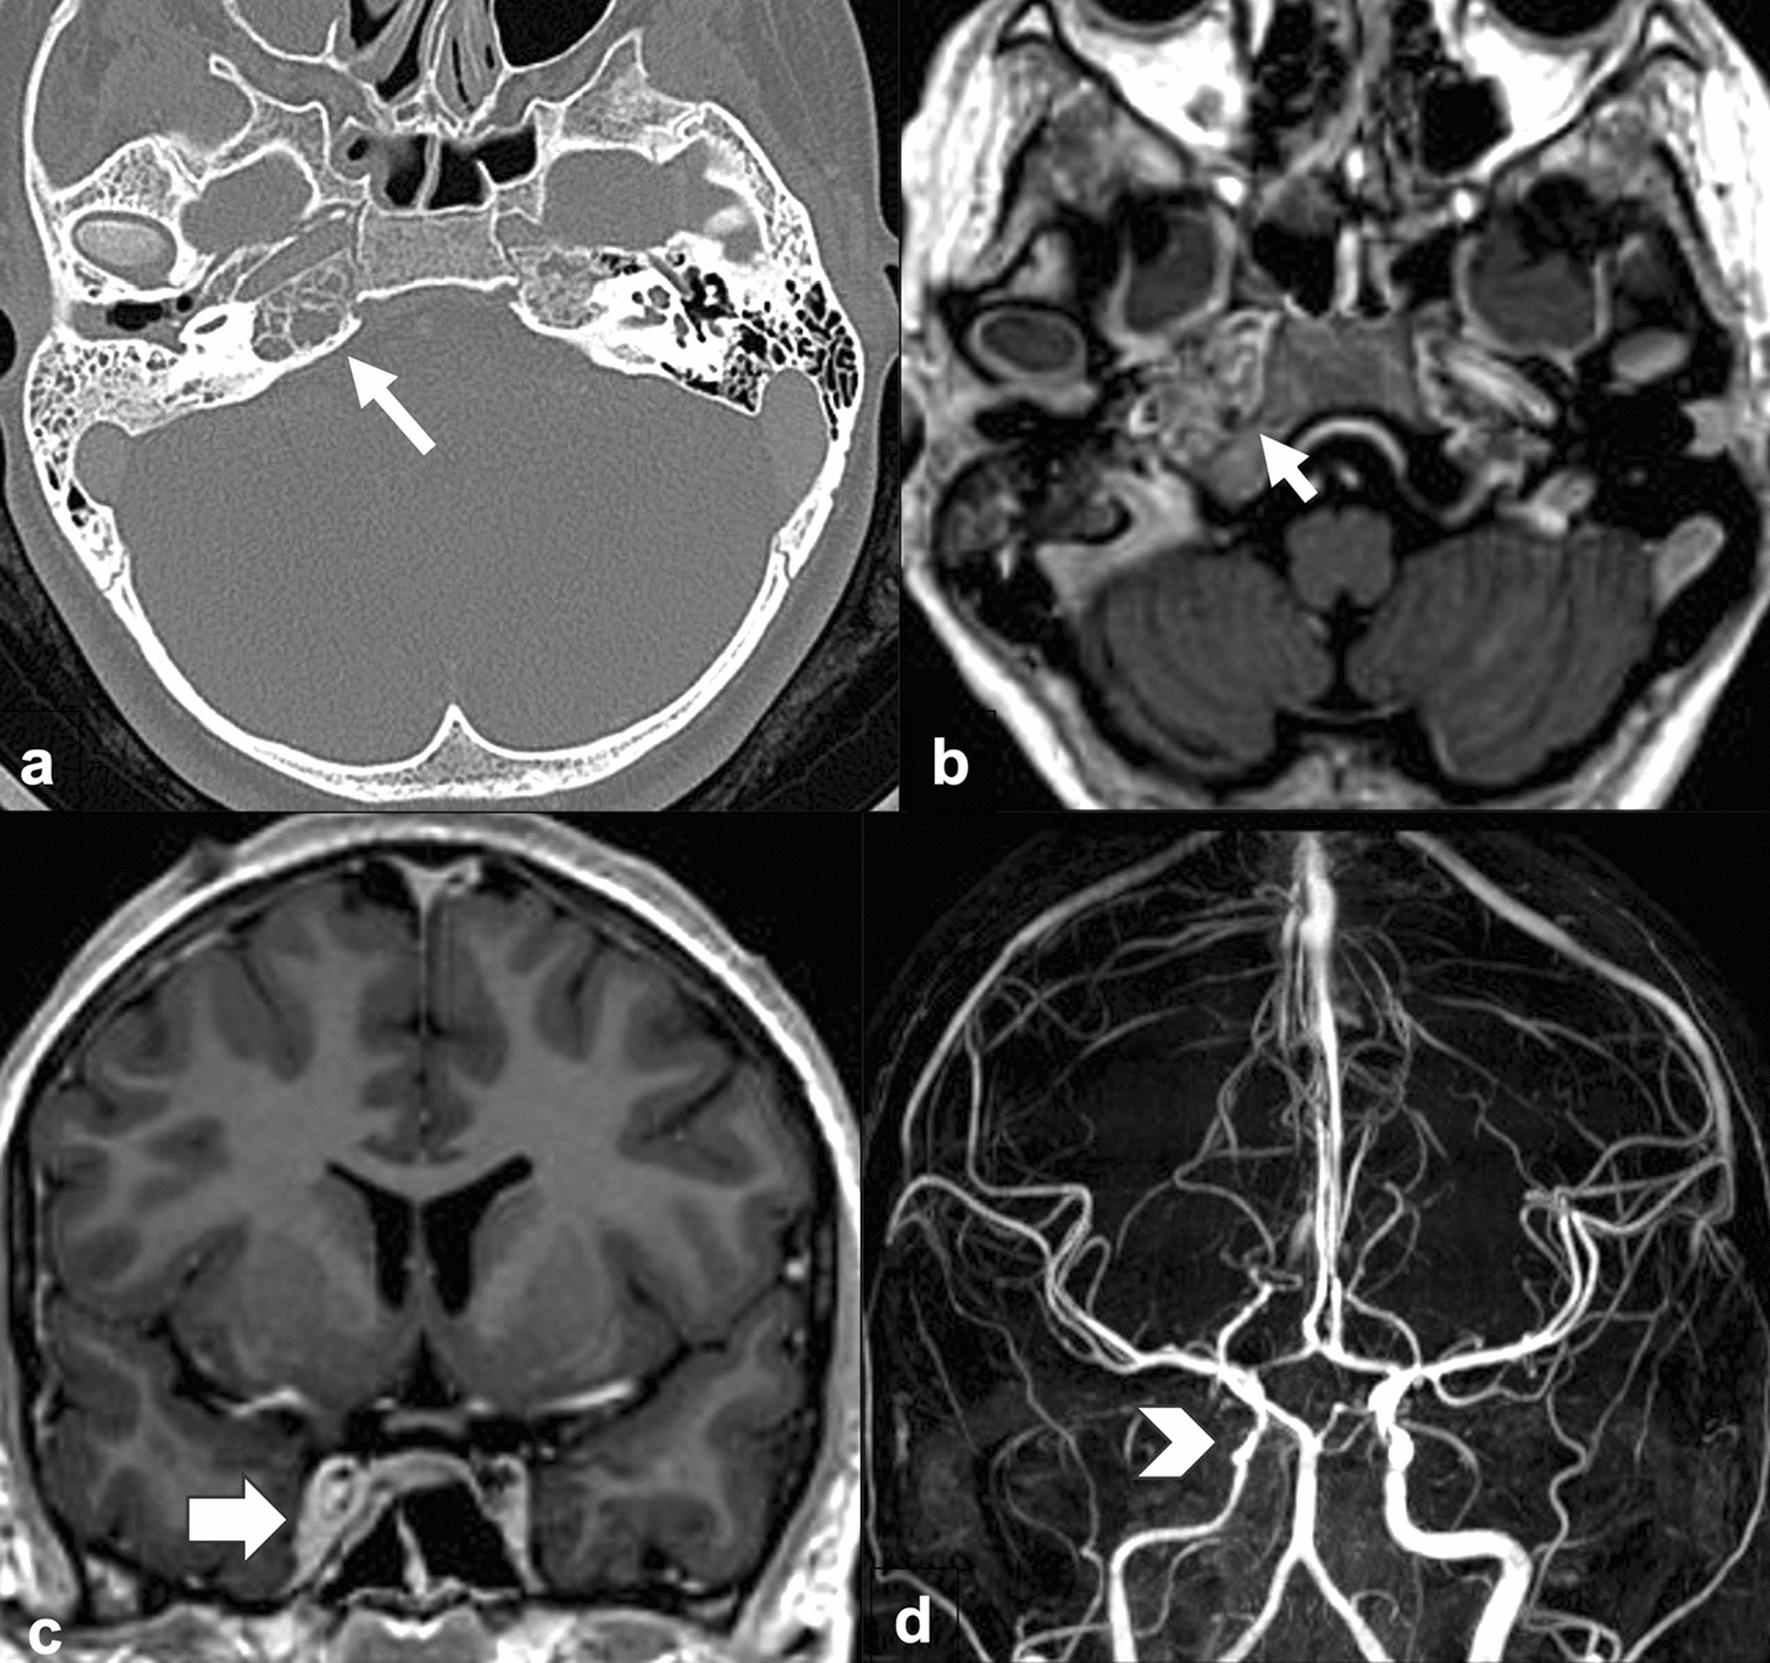

A 12-year-old girl presented with 10 day history of headache, retroocular pain, right 6th cranial nerve palsy and right side otorrhea. Based on clinical presentation, Gradenigo’s syndrome was diagnosed. Head CT demonstrated opacification in the right middle ear cavity, the mastoid air cells and right petrous apex. Asymmetric appearance of the cavernous sinuses was noted concerning for right cavernous sinus thrombosis. Brain MRI showed abnormal enhancement of the right petrous apex and the mastoid air cells in keeping with petrous apicitis and otomastoiditis. Filling defects and bulging of the lateral wall of the right cavernous sinus were seen due to right cavernous sinus thrombosis. There was narrowing of the cavernous segment of the right internal carotid artery (ICA) with associated soft-tissue thickening and vessel wall enhancement consistent with right ICA arteritis due to infectious vasculitis (Fig. 1). The patient was treated with intravenous antibiotics and anticoagulant therapy with improvement of the symptoms.

Fig. 1

Axial (a) head CT image shows opacification in the right middle ear cavity, the mastoid air cells, and right petrous apex (arrow). Axial (b) and coronal (c) T1 weighted images with contrast of brain MRI demonstrate abnormal enhancement of the right petrous apex (short arrow in b) and asymmetric appearance of the right cavernous sinus with filling defects and bulging of its lateral wall (arrow in c). Coronal maximal intensity projection time of flight MRA (d) shows narrowing of the cavernous segment of the right internal carotid artery (arrowhead)